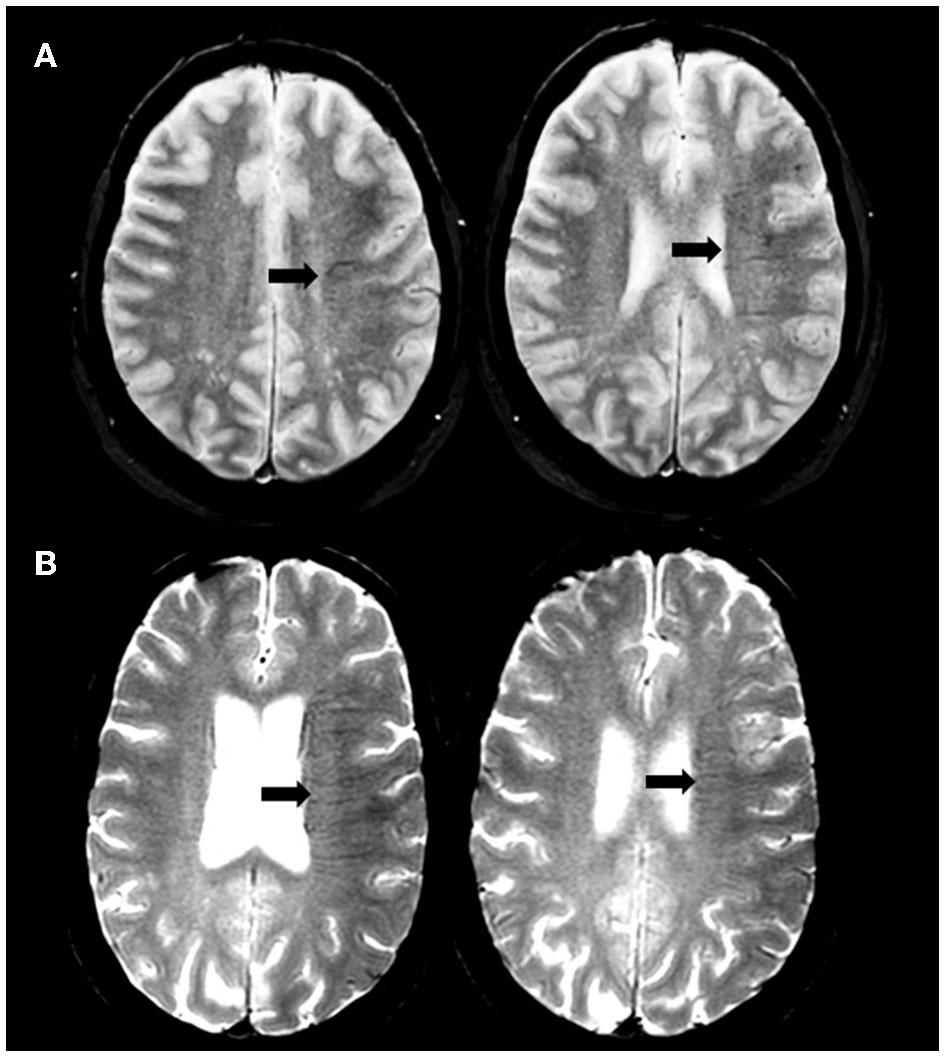

Two experienced physicians in stroke imaging (LR and NN) blinded to clinical and digital angiography data independently reviewed MRI. The brush-sign was defined as multiple hypointense linear and/or branching structures extending through the affected hemisphere, parallel or perpendicular to the outer wall of the lateral ventricles along the course of deep medullary veins on the baseline T2*-weighted gradient-echo sequence (10). The brush-sign was categorized as absent or present and if present classified as moderate, or obvious (Figure 1) (5). Any discrepancies were resolved by a third expert (ABS). DWI-ASPECTS was assessed on admission DWI sequence without further details on the affected brain regions (11). White matter hyperintensities (WMHs) were assessed on the FLAIR sequence according to the Fazekas scale; both the periventricular and subcortical components of the scale were evaluated (12). Cerebral microbleeds (CMB) were rated on GRE T2*WI according to the MARS criteria (13). The collateral status was determined on digital subtraction angiography (DSA) images according to the score of the American Society of Interventional and Therapeutic Neuroradiology/Society of Interventional Radiology (ASITN/SIR) and considered as poor for ASITN/SIR score < 3 (14). Reperfusion status was considered as successful if Thrombolysis in Cerebral Infarction (TICI) score was 2b or 3 (14). A CT scan was performed on day 1. Symptomatic intracerebral hemorrhage (sICH) was defined according to the SITS-MOST definition (15).

Figure 1. Illustration of brush-sign. Axial gradient-recalled echo T2*-weighted imaging showing moderate (A) and obvious (B) brush-sign.